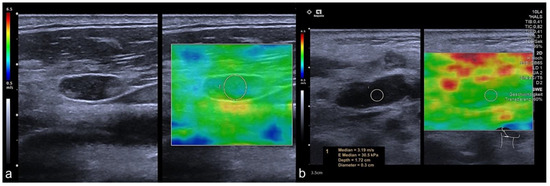

2.2. Imaging Protocol

2.3. Perfusion Analysis

3.4. Infracentimetric CLN